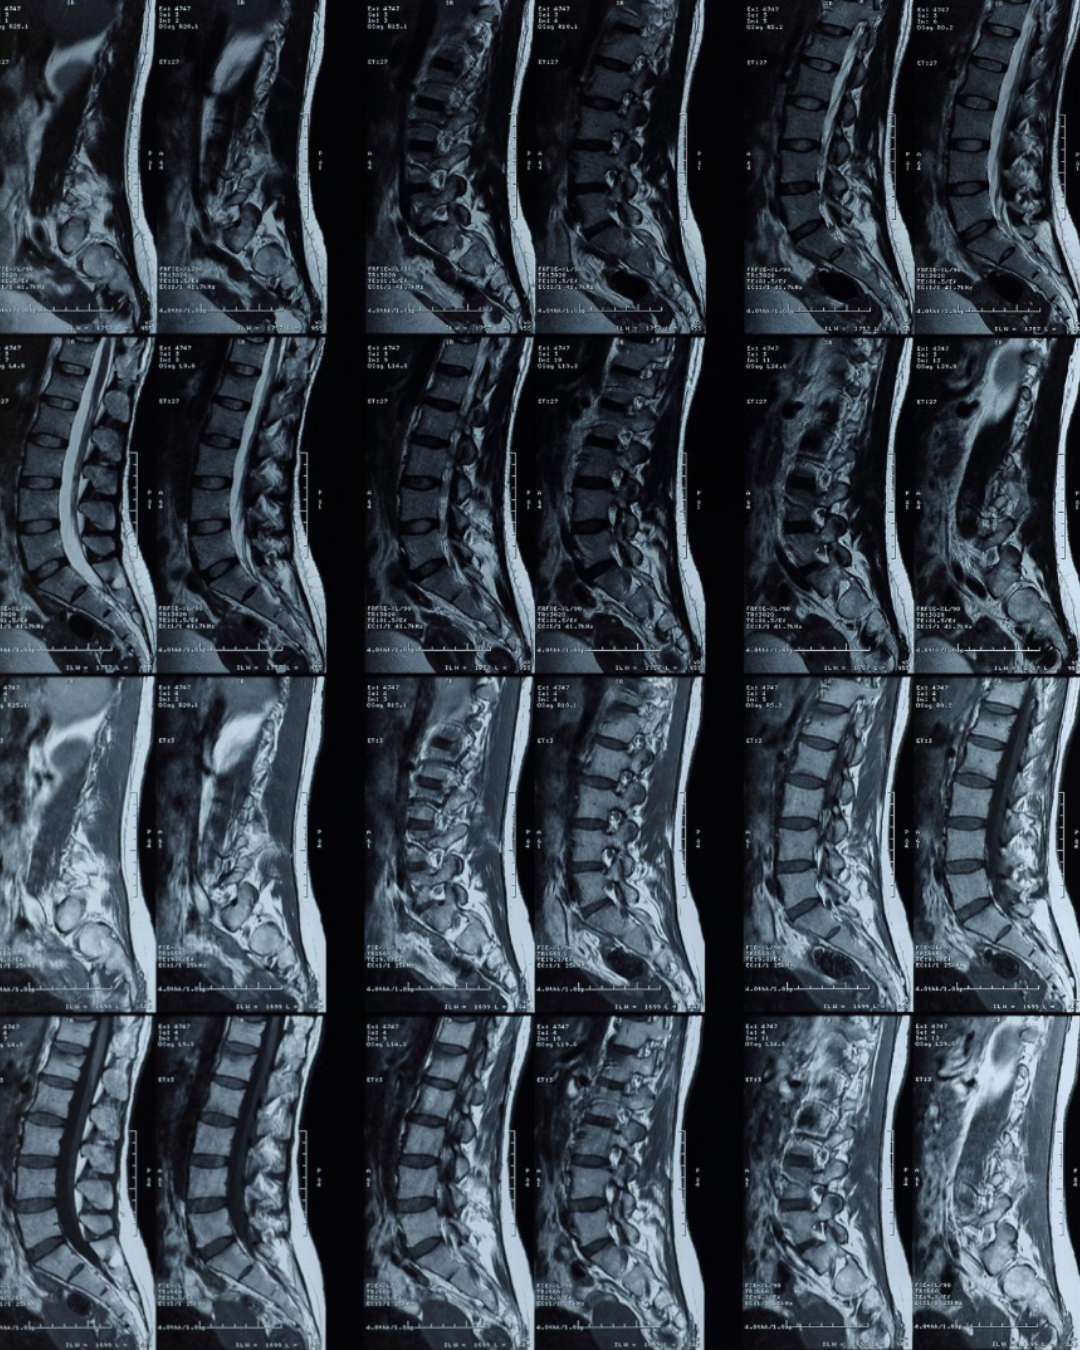

Why? Because modern research consistently shows that structural findings alone do not reliably explain pain.

Research shows that structural findings on imaging are common in people without pain, particularly as age increases. Systematic reviews have demonstrated that many people with no pain or disability show findings on imaging such as:

• Disc degeneration

• Disc bulges or protrusions

• Facet joint changes

• Age-related spinal changes

These findings increase with age and are often part of normal human variation rather than indicators of injury or dysfunction.(Brinjikji et al., 2015; Brinjikji et al., 2015)

Key takeaways from this literature review include:

• Prevalence of disc degeneration in asymptomatic individuals increased from 37% of 20-year-old individuals to 96% of 80-year-old individuals

• Prevalence of disc bulges in asymptomatic individuals increased from 30% of those 20 years of age to 84% of those 80 years of age

• Prevalence of disc protrusion in asymptomatic individuals increased from 29% in those 20 years of age to 43% in those of 80 years of age

• Prevalence of Annular fissures in asymptomatic individuals increased from 19% of those 20 years of age to 29% of those 80 years of age.